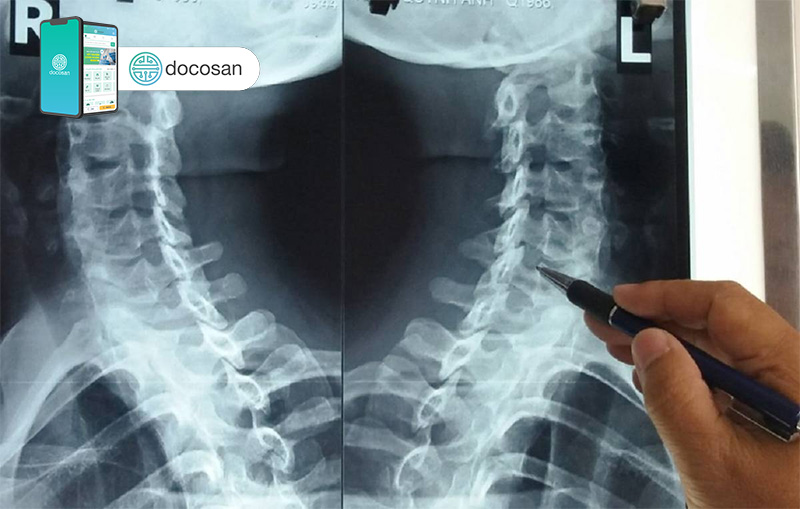

Đa phần bệnh gai cột sống không có dấu hiệu hoặc triệu chứng nào rõ ràng. Người bệnh thường chỉ nhận ra trong một lần thăm khám tổng quát, chụp X-Quang cột sống hoặc khi gai xương phát triển, chèn ép và gây triệu chứng, hay gặp là cảm giác đau và giảm khả năng vận động của khớp cột sống.

Gai cột sống phát triển cùng với sự sự lão hoá của con người. Thực tế, các gai xương được xem là một phát hiện bình thường trên phim X-Quang hoặc MRI cột sống ở người lớn.

- X-Quang cột sống: Là xét nghiệm hình ảnh đơn giản, tiết kiệm để tầm soát, kiểm tra và phát hiện gai xương, cũng như mức độ chèn ép thần kinh.